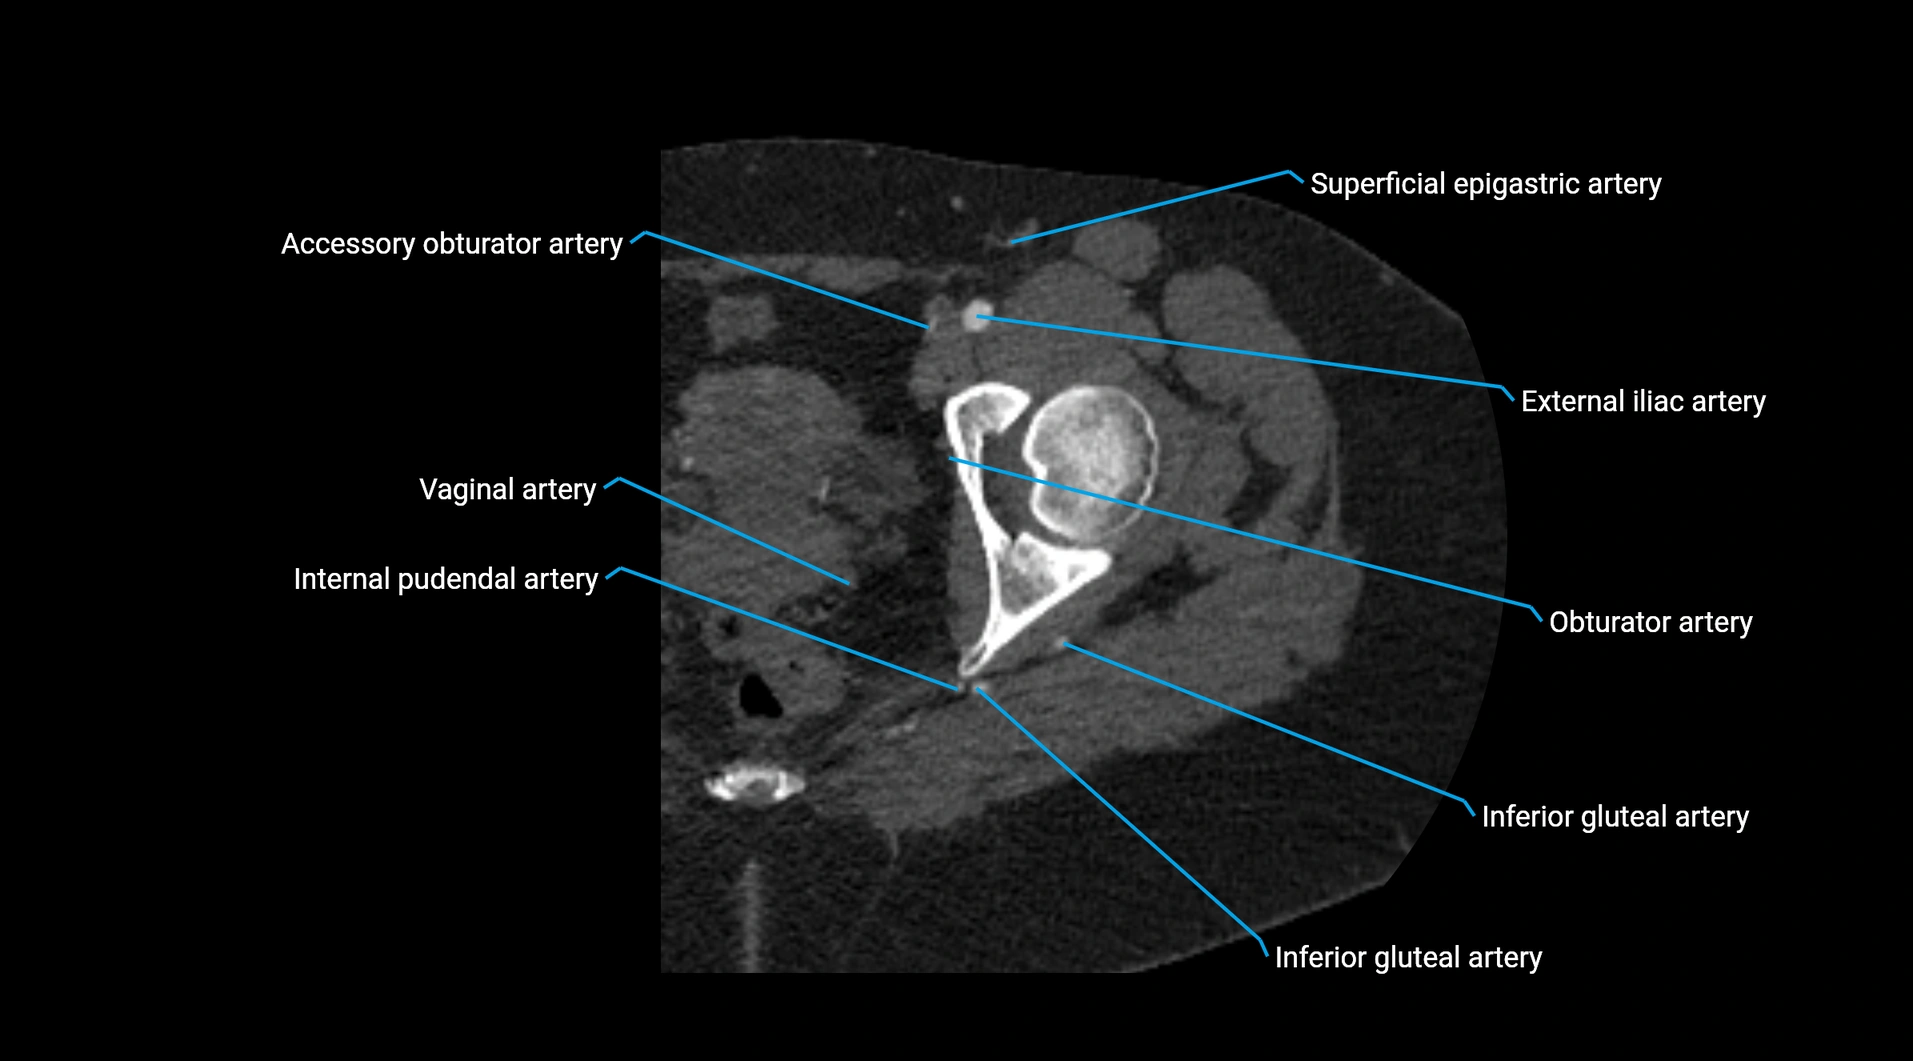

CT images

image